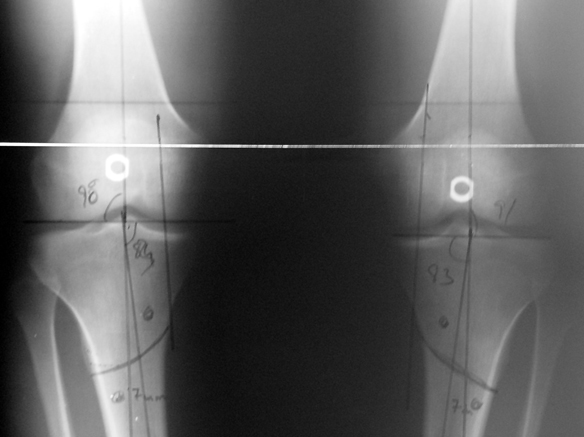

The patient lies is supine position at a traction table and legs are crossed with the uninvolved leg at the bottom. The medullary cavity is penetrated through piriform fossa using the standard method, and medulla is reamed 1.5 mm thicker than the nail to be used, over a guidewire. Proximal femur is reamed more, because the intramedullary nail is thicker proximally. The osteotomy site is planned at the X-Rays. It is important that at least 8 cm. of nail remains distal to the osteotomy site after the completion of the lengthening procedure. Percutaneous corticotomy is performed. The guide wire is advanced distally in order to measure the length of the nail. An intramedullary nail of apropriate length is placed. In the end, the nail is interlocked proximally, a suction drain is placed and the fist step of the operation is completed.

The application of the external fixator: Three Schanz screws are placed distally and three screws are placed proximally. At least 1 mm of distance shall remain between the screws and the nail.

In selected cases, we prefer to use a combination of a unilateral dynamic axial fixator and an interlocked intramedullary nail, in order to protect the length and alignment after the completion of the lengthening procedure. As a prerequisite for this technique, the narowest diameter of the medullary cavity shall be wider than 7 mm and the length of the nail segment distal to the osteotomy site shall be at least 8 cm. after the completion of the lengthening procedure.The intramedullary nail neutralizes shear and bending forces on femur during lengthening, shortens external fixation time, and protects newly formed bone against fractures. In our series, subtrochanteric osteotomy was performed in one case. No varus angulation occured despite the intramedullary nail.